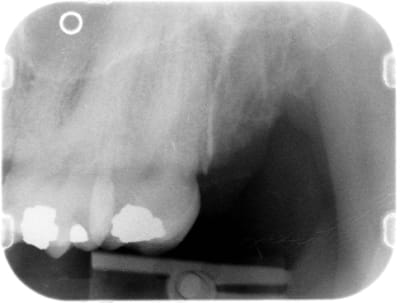

on voit qu'effectivement elle avait de belles hanches...

l'image est trompeuse, on voit le palais osseux en perspective mais le trait vertical d'alvéolectomie juste en distal de 27 reflète la réalité clinique.

belle regularisation de crete osseuse, que tu ne peux même pas coter car faite au cours de la séance d'extraction.

Par contre, moi je vois sur tes radios, des amalgames, qui mériteraient eux aussi des avulsions, mais beaucoup plus conservatrices ;)

Vu les clichés elle semble accessible alors pourquoi pas: endo-ic-co avec une éventuelle élongation coron. ?